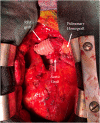

The arterial switch operation is the gold-standard treatment for dextro-transposition of the great arteries. Long-term follow-up data are beginning to reveal its natural history and associated late complications, including various reoperations for those complications. Given the unique anatomy and the increasing longevity of these patients, there is a need for effective surgical repair options to address aneurysmal and degenerative changes in both neoaortic and pulmonic roots. Thereby, we describe our technique and the novel considerations for prosthetic choice with reconstruction of both the neoaortic root and pulmonary artery, with satisfactory postoperative results.